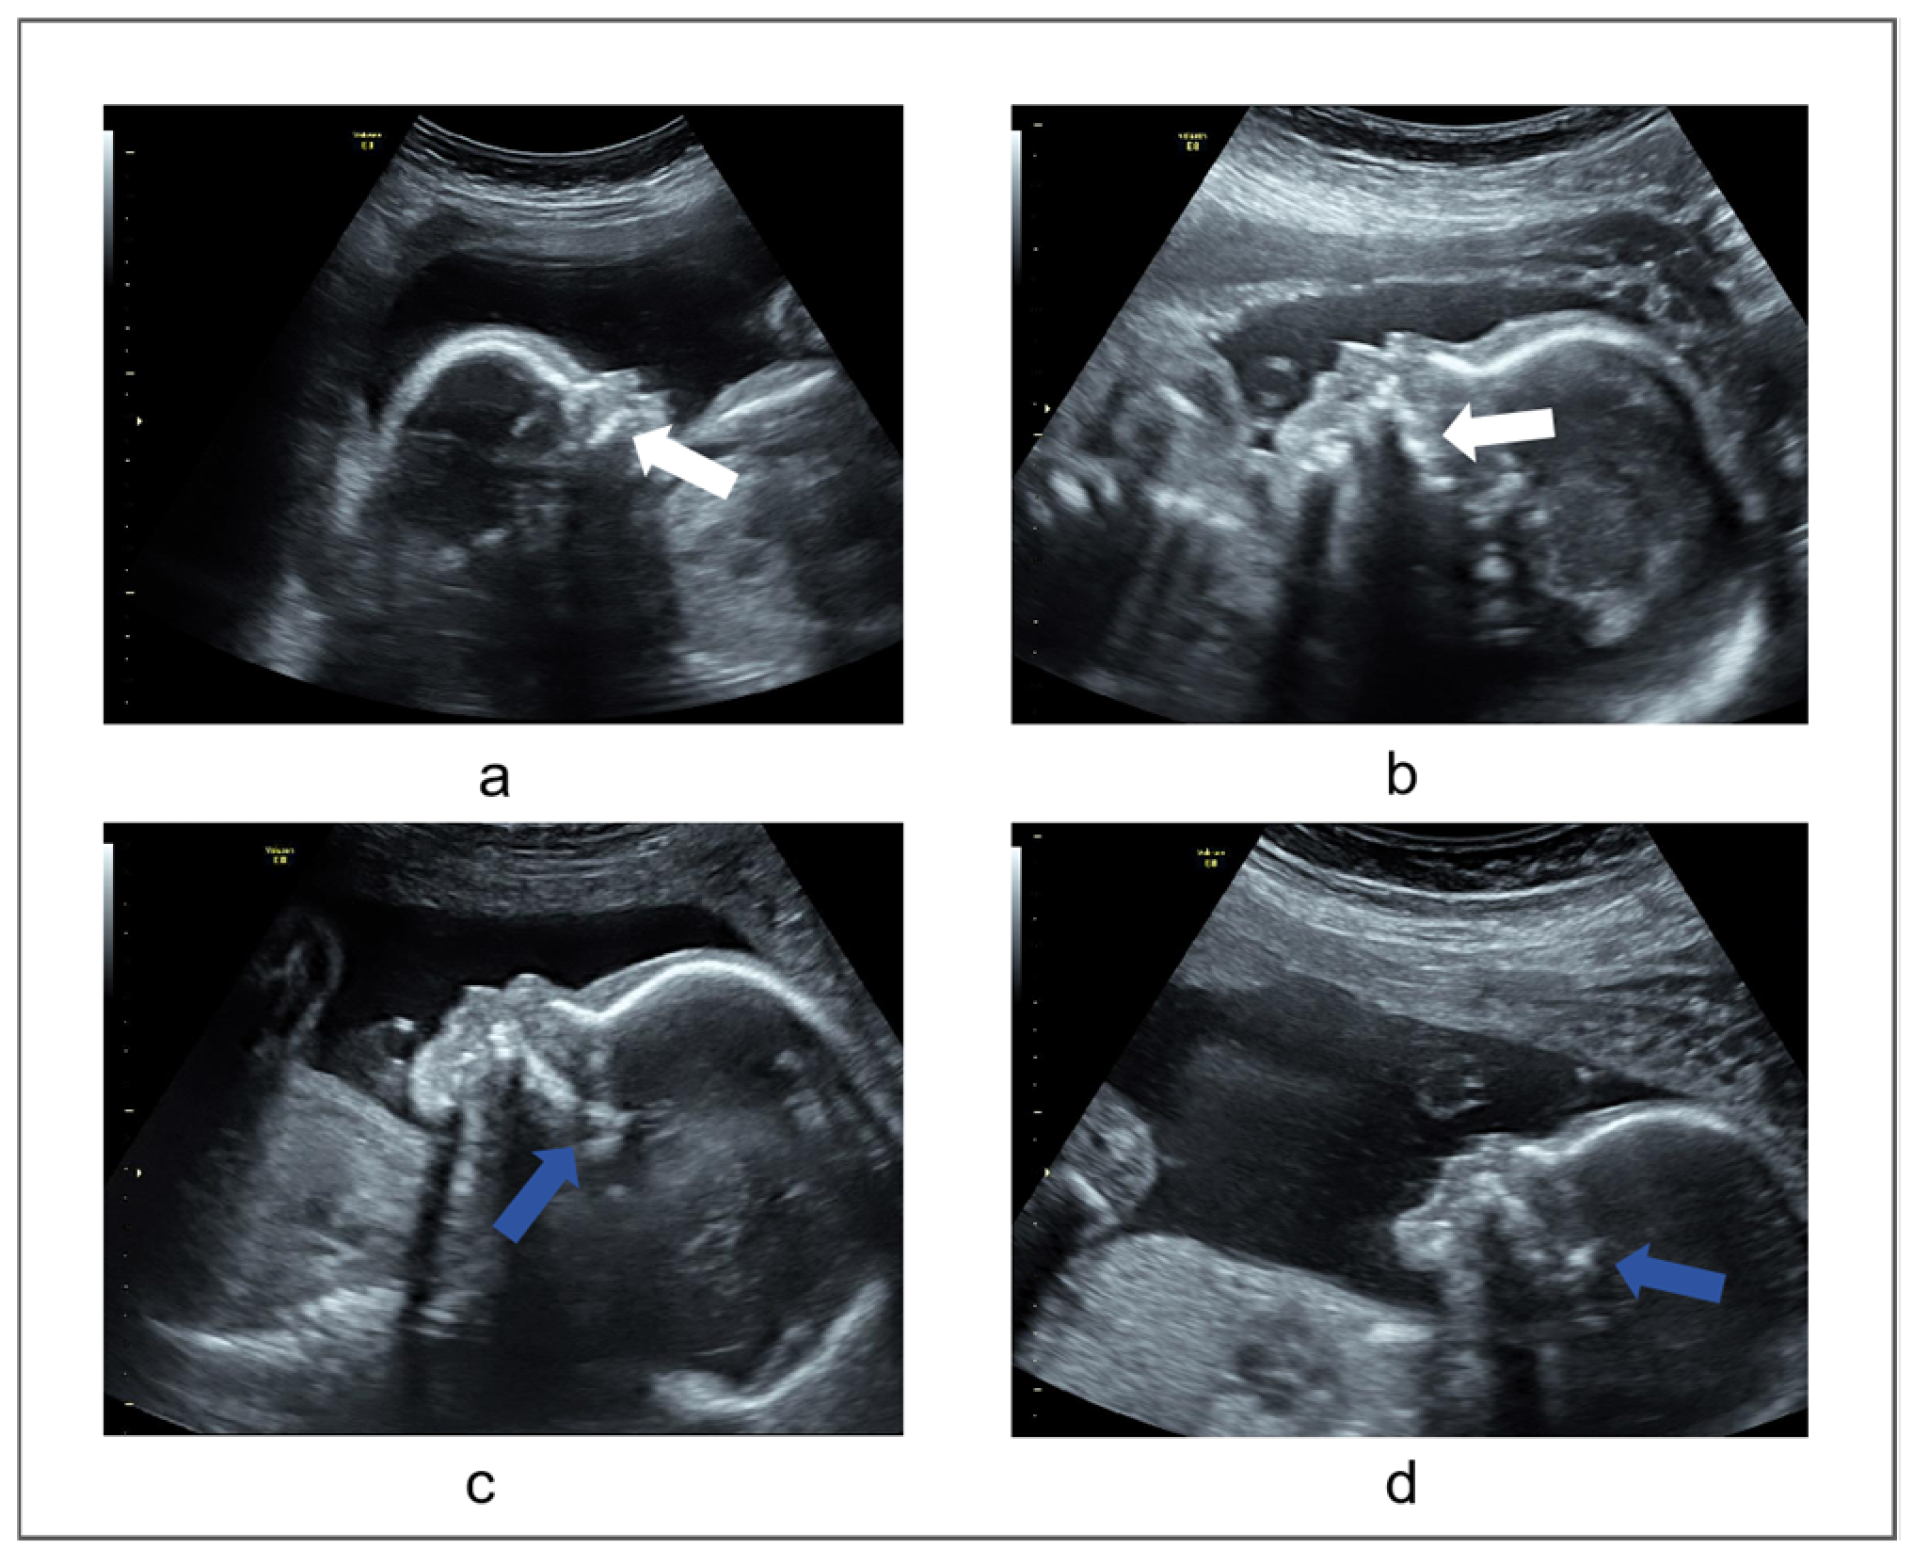

- Poor image quality may affect the doctor’s judgment. Due to the complex interaction between US waves and the biological tissues of the mother and fetus, ultrasound images can be affected by speckle noise, acoustic shadow, motion blurring, missing boundaries, and poor picture clarity. This situation can affect the physician’s measure result. For instance, the definition of the palatal margin might become indistinct, evident from the white arrow depicted in Figure 2a,b;

- Judgment of critical structures on ultrasound images is more difficult. The anterior segment of the palate stands out as the most prominent, while the posterior region might exhibit thickening and irregularity, as illustrated by the blue arrow in Figure 2c,d, which can affect the physician’s judgment;